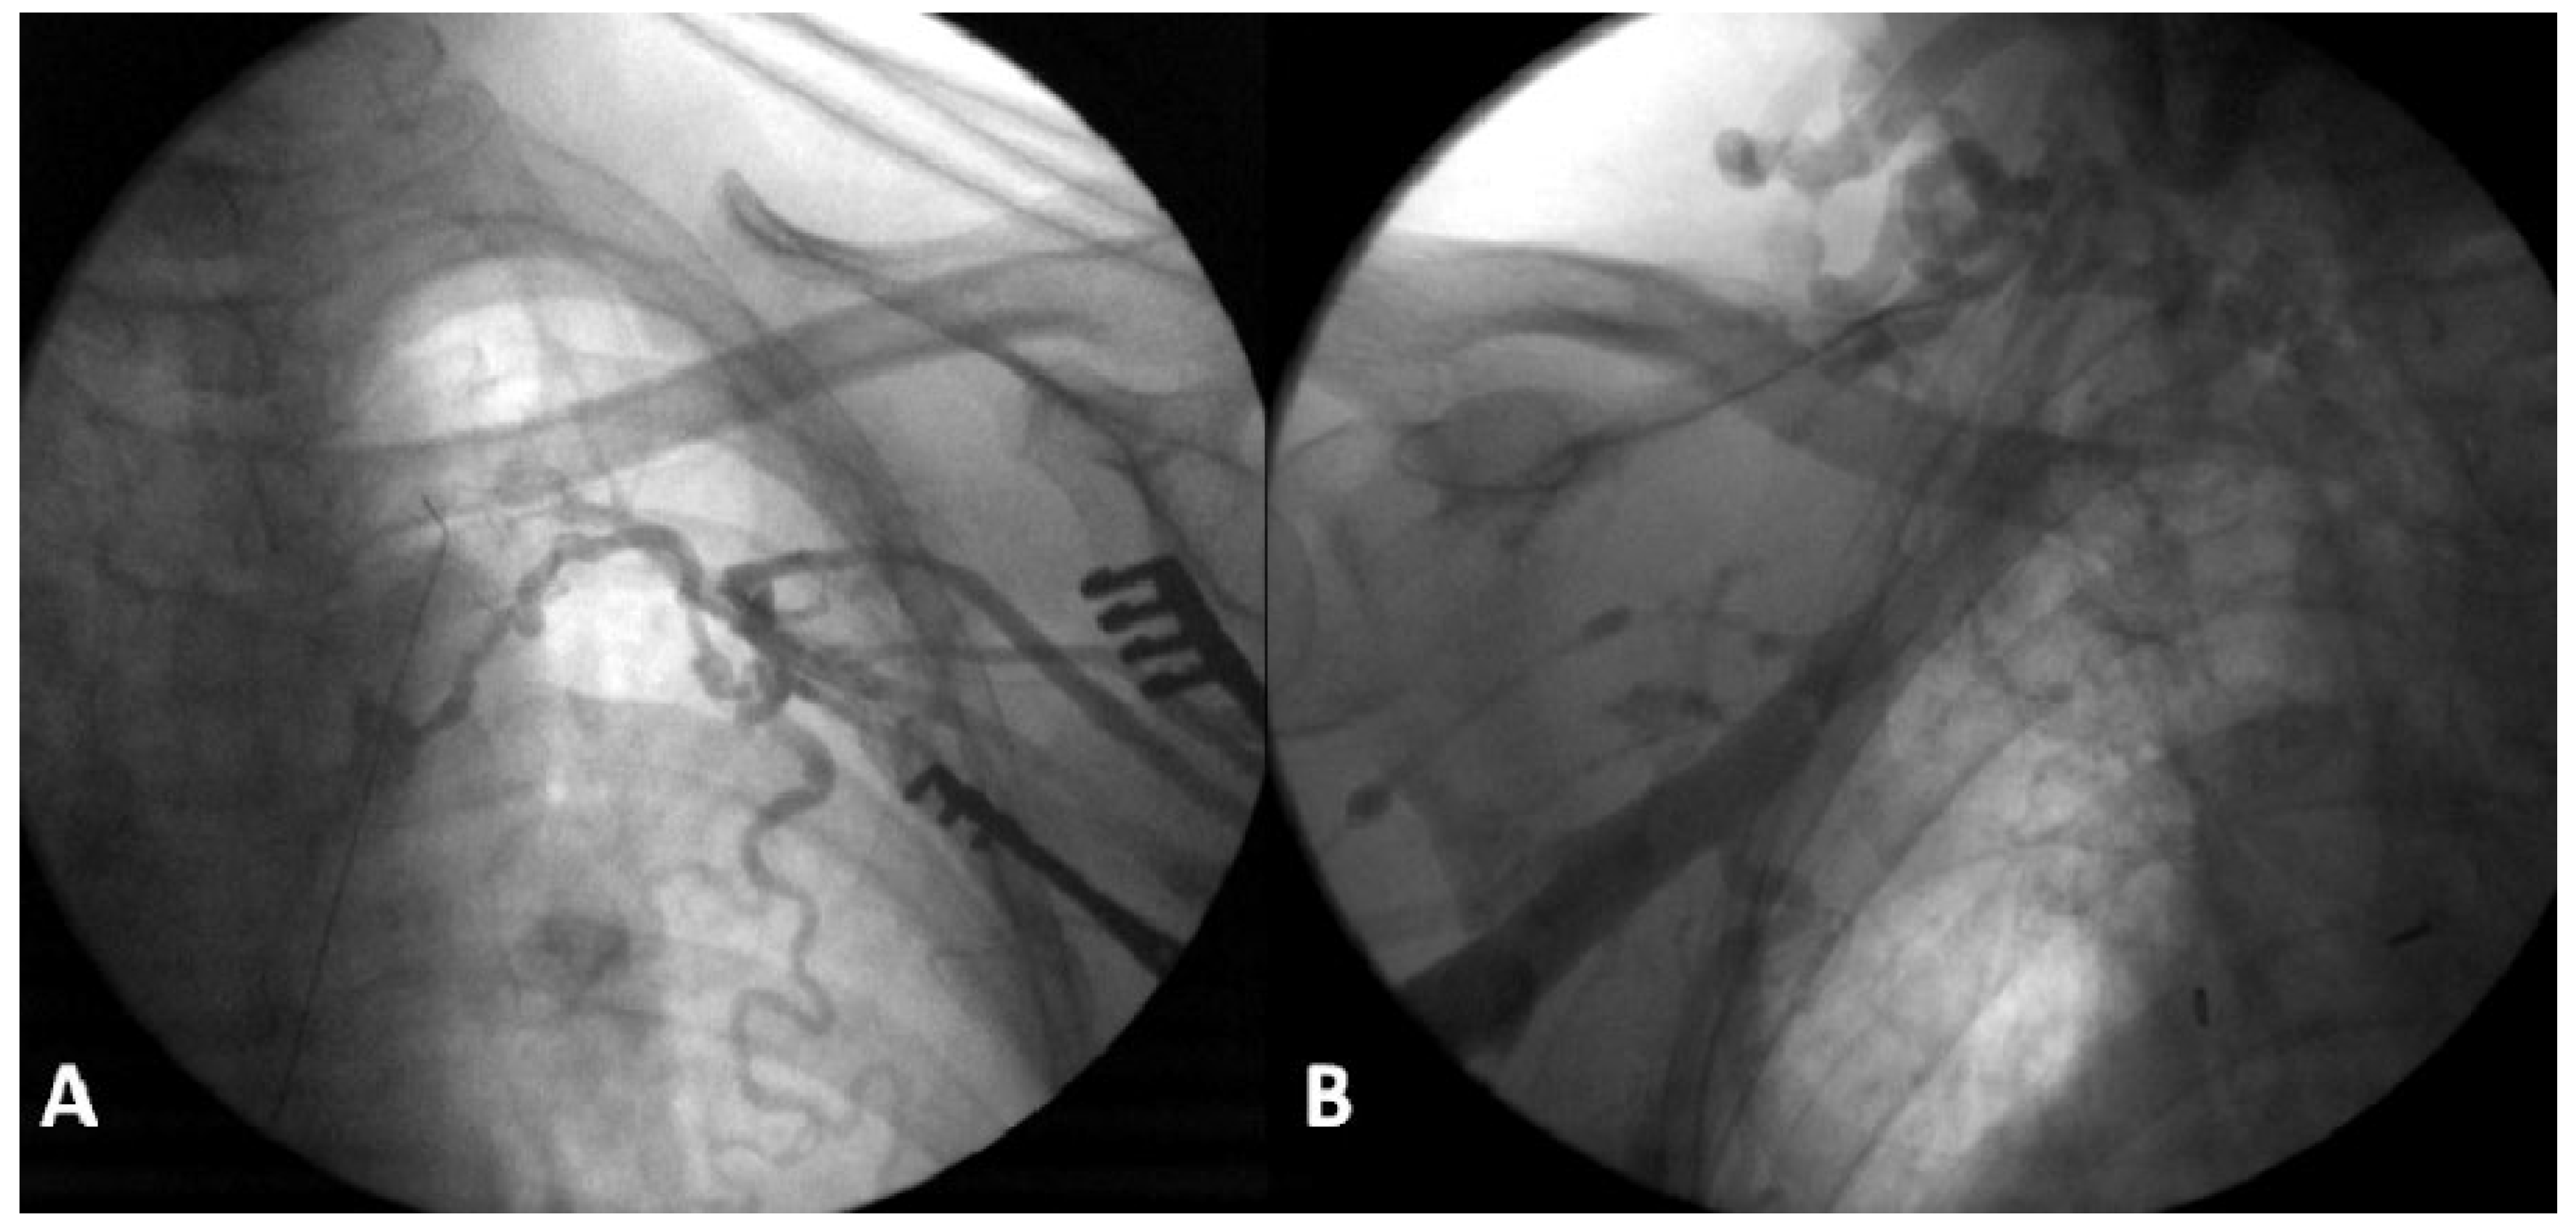

Pacemaker implantation: The right femoral vein was punctured in the groin, approximately 3 cm below the iliac ligament. A deflectable 8.4F guiding catheter (Medtronic® Minneapolis, MN, USA) was advanced over a 0.35 inch guidewire into the right atrium. A 69 cm Medtronic Select Secure 3830 lead was implanted in the right atrial appendage (Figure 2 and Figure 3). This is a 4.1 French lumenless fixed-helix active-fixation pacing lead that requires a guiding catheter for positioning. This model was chosen because of its length (59 cm and 69 cm available), its stability, and its high flexibility and tensile strength to accommodate increased stress due to hip flexion. The electrical parameters were normal and atrial pacing at 130 bpm revealed 1:1 conduction (with normal QRS width). For this reason, and to avoid excess foreign body material, a ventricular lead was not implanted. The lead was connected to a Medtronic Relia SR pacemaker, which was placed in a pocket in the upper anterior thigh. The wound was closed with resorbable subcuticular monofilament suture and a waterproof dressing was applied. The patient was discharged on the day after the procedure, with the device programmed to AAIR 60– 120 bpm. The wound healed well, without any discomfort caused by the generator pocket (Figure 4). The patient had marked symptomatic improvement, with rate histograms showing good adaptation despite the unusual generator location (Figure 5). Follow-up for more than 4 years has been uneventful, with stable electrical parameters.

Figure 2. Device implantation. (A) Deflectable guiding catheter positioned in the right atrium over a guidewire via the right femoral vein. (B) Lead insertion into the right atrium via the guiding catheter. (C) Formation of a loop to allow sufficient slack and stabilise the lead. (D) Generator positioning in the superior and anterior part of the right thigh.